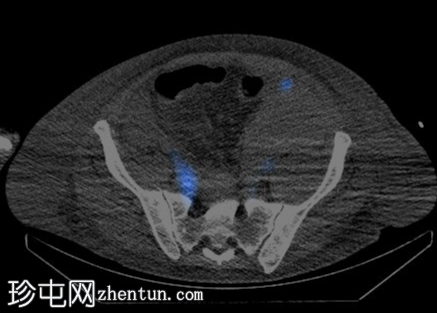

CT

腹部和盆腔增强CT扫描证实左下腹血肿,密度呈层状分布,并可见少量微小高密度灶,可能提示造影剂外渗。